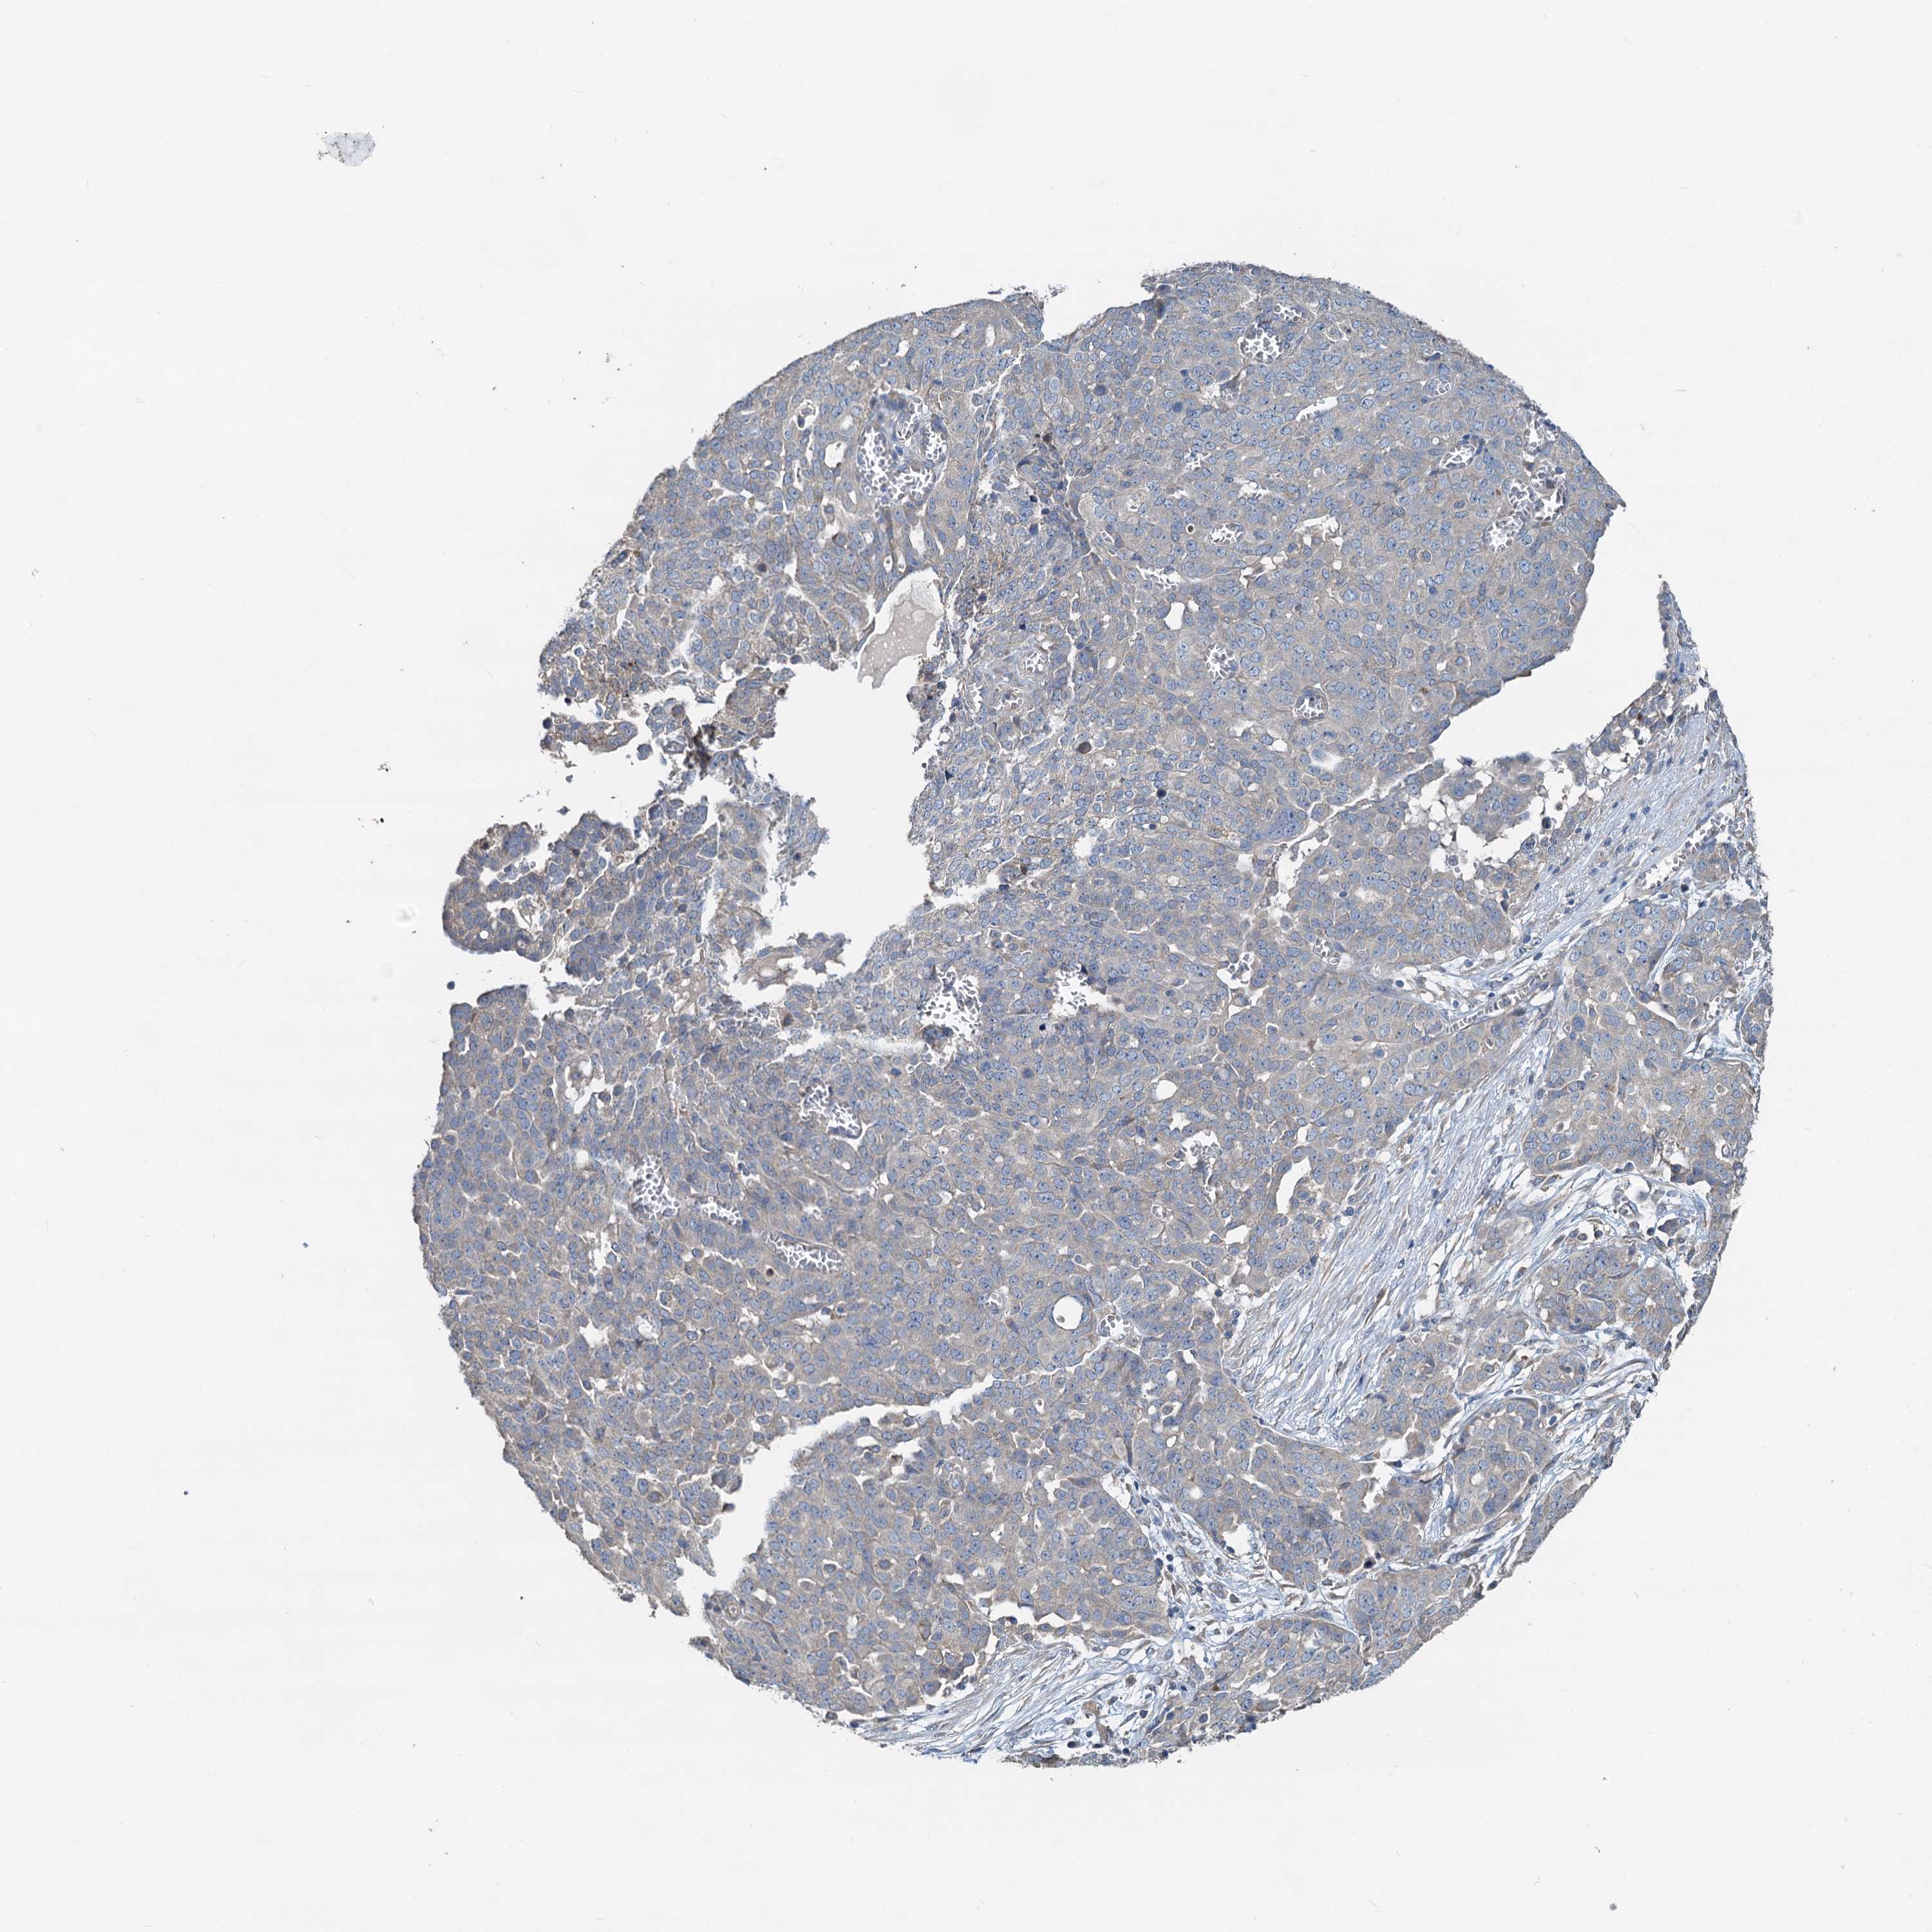

OVARIAN CANCER - Protein expressioni

A mouse-over function shows sample information and annotation data. Click on an image to view it in a full screen mode. Samples can be filtered based on level of antibody staining by selecting one or several of the following categories: high, medium, low and not detected. The assay and annotation is described here.

Note that samples used for immunohistochemistry by the Human Protein Atlas do not correspond to samples in the TCGA dataset.

Antibody stainingi

Antibody staining in the annotated cell types in the current human tissue is reported as not detected, low, medium, or high, based on conventional immunohistochemistry profiling in selected tissues. This score is based on the combination of the staining intensity and fraction of stained cells.

Each image is clickable and will lead to virtual microscopy that enables deeper exploration of all samples and also displays staining intensity scores, fraction scores and subcellular localization as well as patient and tissue information for each sample.

Antibody HPA040092

Staining

High

Medium

Low

Not detected

Intensity

Strong

Moderate

Weak

Negative

Quantity

>75%

75%-25%

<25%

None

Location

Nuclear

Cytoplasmic/membranous

Cytoplasmic/membranous,nuclear

Cystadenocarcinoma, serous, NOS

Carcinoma, endometroid

Cystadenocarcinoma, mucinous, NOS

Carcinoma, NOS